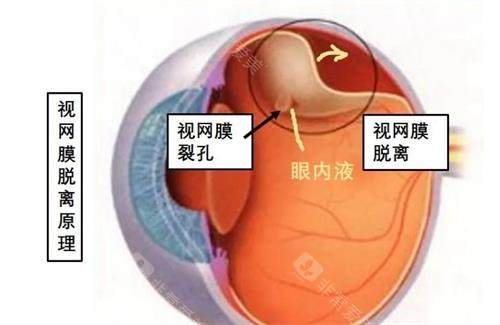

作为首都医学大学附属北京同仁医院眼底病科的“定海神针”,他擅长复杂眼底病诊疗,尤其对视网膜脱离、糖尿病视网膜病变等疾病的手术处理堪称业内标杆。